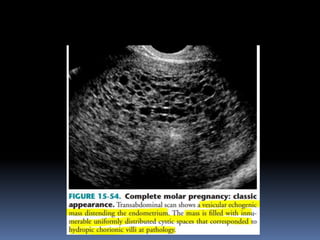

This document contains an image gallery from Dr. Mohit Goel showing various uterine anomalies and ovarian cysts. It includes images of an arcuate and unicornuate uterus, endometritis, a twisted ovarian pedicle, dermoid cysts of varying sizes and echogenicity containing hair, fat, and calcifications, and a combination dermoid cyst showing both mesh and plug structures. The gallery provides ultrasound images of different gynecological conditions for medical education and reference.